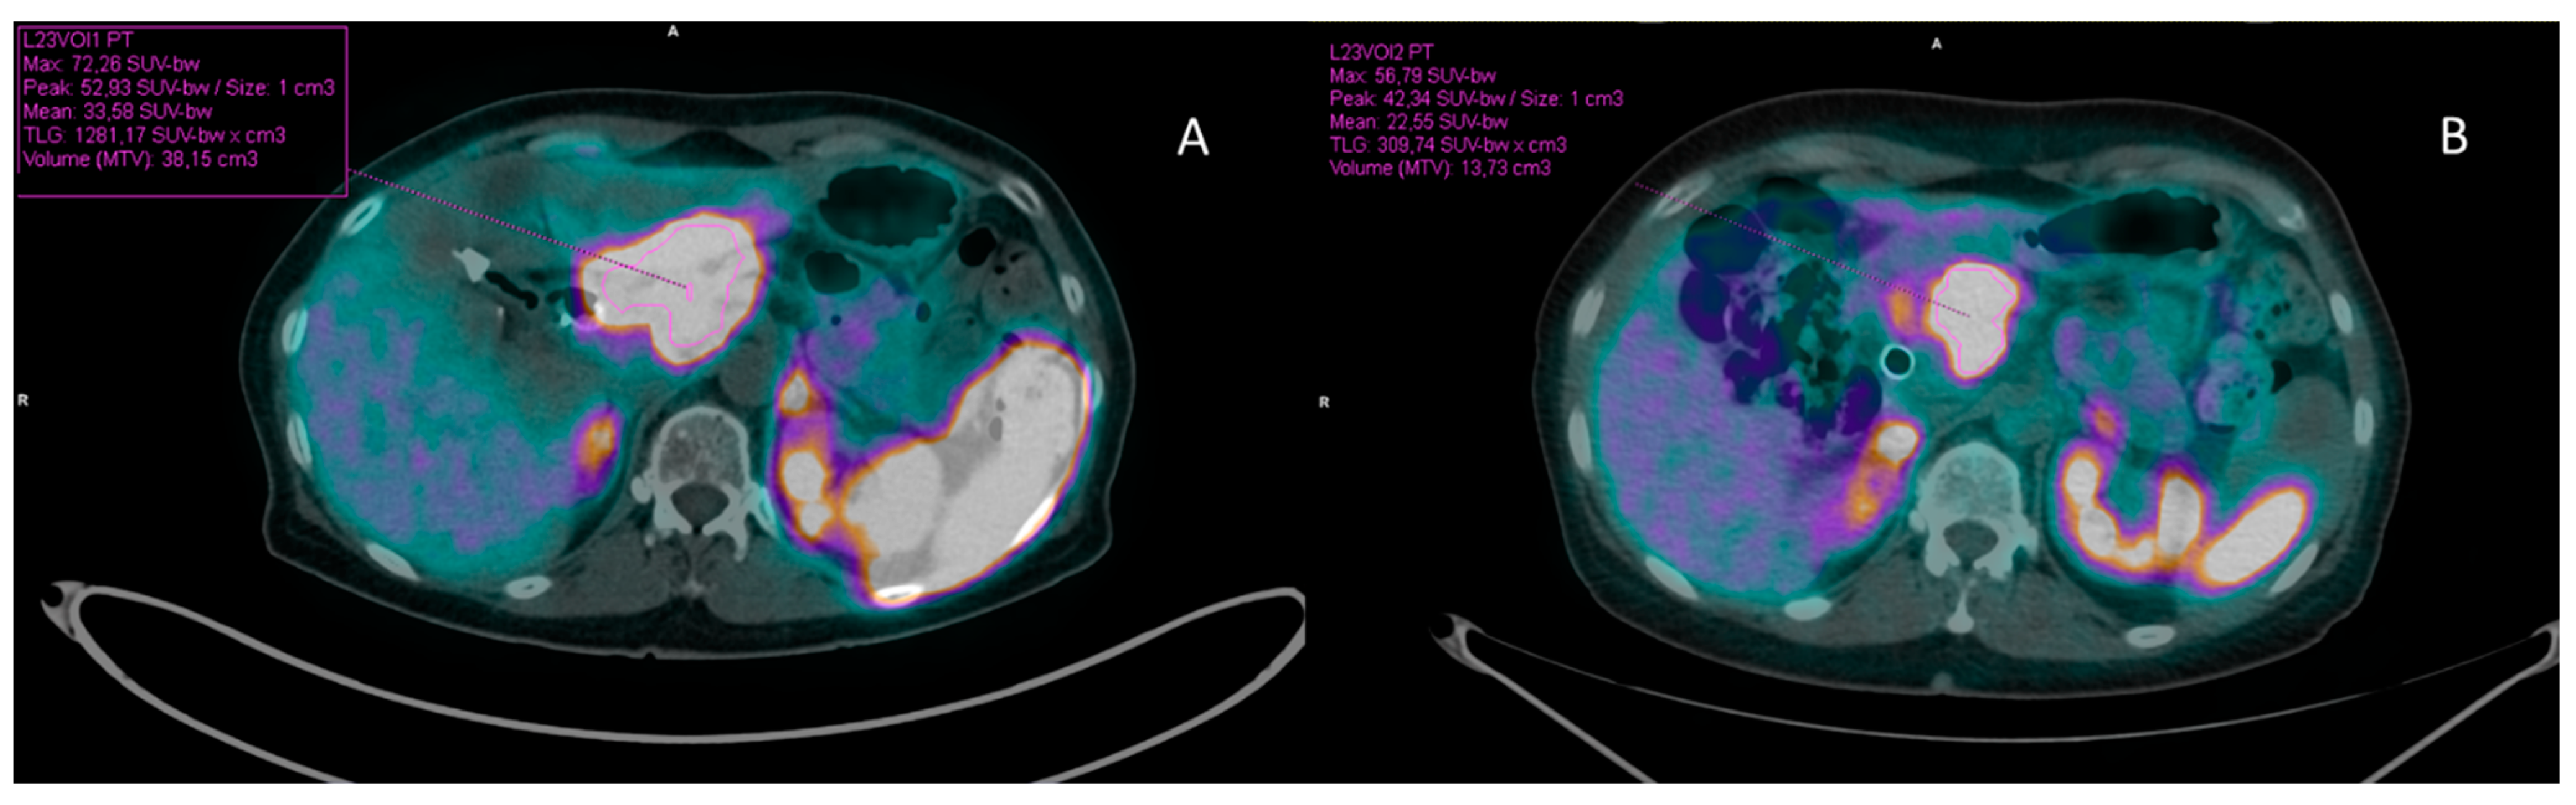

2.3. Images Acquisition and Evaluation

3.2.1. Total Tumor Burden Analysis

3.2.2. Liver Tumor Burden Analysis